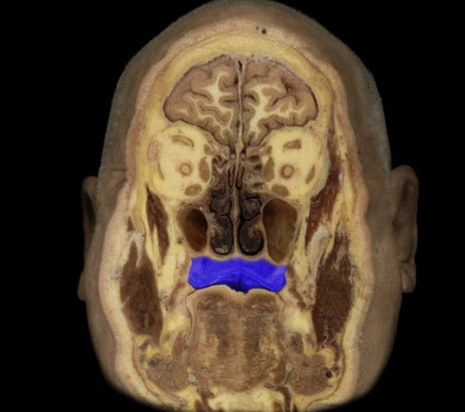

What structure is highlighted in blue?

Hard palate